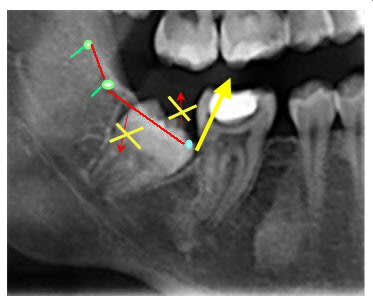

Un orthodontiste me refère une patiente avec le même problème au niveau des dernières molaires (patientes 12 ans) aux ma=xillaires inférieures; il me demande d'exposer les dents. Comment le faite-vous? en profitez-vous pour faire un peu d'ostéoplastie en distal? Dans mon cas l'arcade de 6 à 6 est en place.La distalisation des 6 a empêché l'éruption des 7.

Probl me d axe.. - Eugenol

Redresseur d axe tiwjog - Eugenol